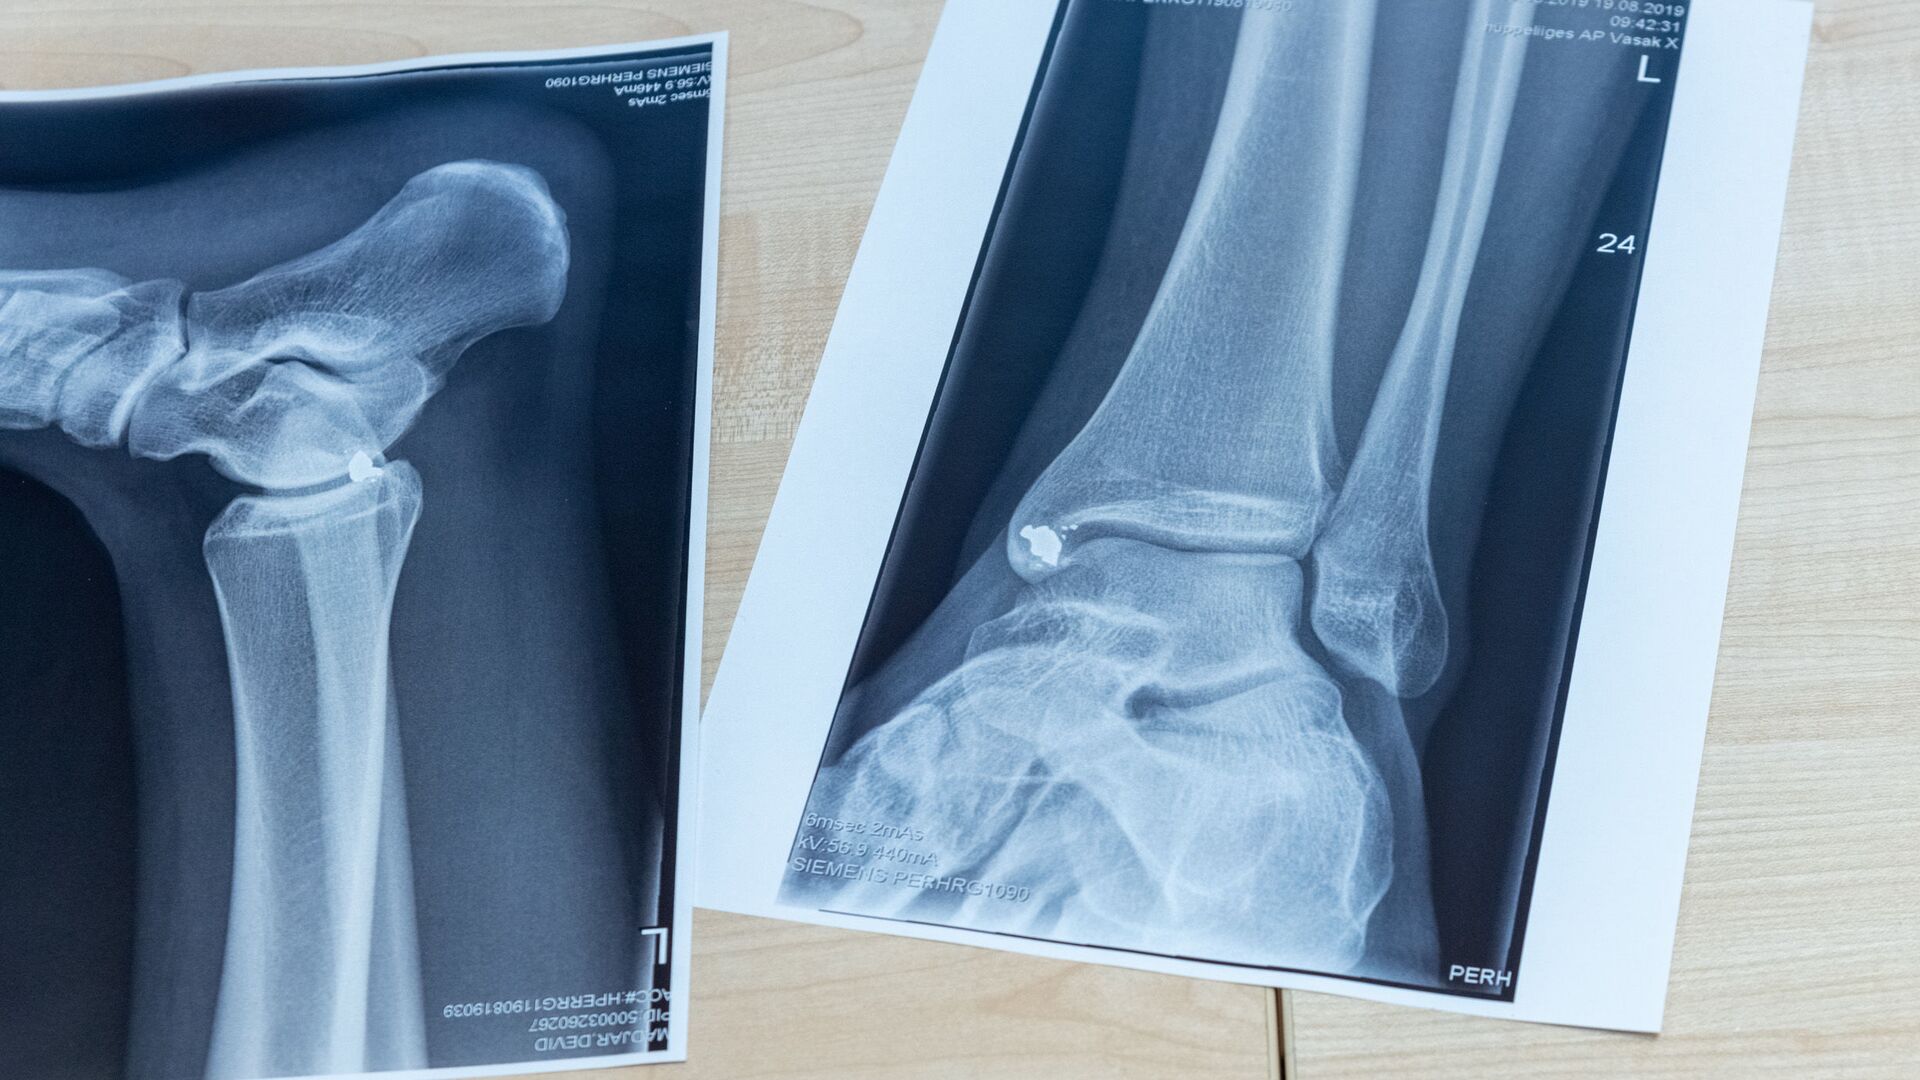

РИГА, 17 апр - Sputnik. В феврале этого года Екабпилсская больница получила жалобы на некачественную работу двух врачей-травматологов и приостановила работу отделения травматологии. Сейчас экстренную помощь пациентам оказывают помощники врачей или хирурги, а в более сложных случаях людей переводят в другие стационары - чаще всего в Мадону.

Больница объявила набор сразу на несколько вакансий: заведующего отделением травматологии, травматолога, ортопеда и дежурного травматолога. Медикам предлагают около шести тысяч евро брутто, а также возможность работать на неполную ставку. Но желающих пока нет.

Как отметил заместитель председателя думы Екабпилсского края по вопросам здравоохранения Айварс Ванагс, поиск травматологов напоминает "поиск иголки в стоге сена". Единственный кандидат хотел зарплату в 15 тысяч евро.

Если в течение ближайших двух месяцев специалистов найти не удастся, местные власти намерены начать переговоры с министерством здравоохранения о дальнейших шагах. Один из возможных сценариев - полное закрытие отделения до появления новых врачей.